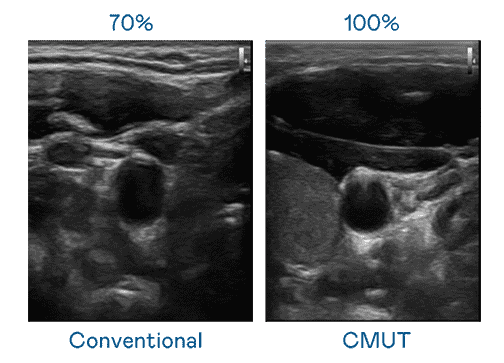

CMUT 技术是一种用电容式微机电元件来产生超音波讯号的技术。。。与传统 PZT 压电式技术相比,,CMUT 频宽增加 30%,,,更宽频的超音波讯号让影像解析度大幅提升,,,,是实现高影像品质医疗超音波扫描、、、、促进精准医疗发展的关键技术。。

超音波影像的解析度高低,,,,首先取决于探头能发出的讯号频宽。。口袋牛店 CMUT 可提供高清晰的超音波讯号,,提供高频宽、、、高灵敏度、、、、影像纹理细节更高的超音波影像,,协助医护人员缩短影像判读时间及利用精准的医疗影像进行诊断。。。